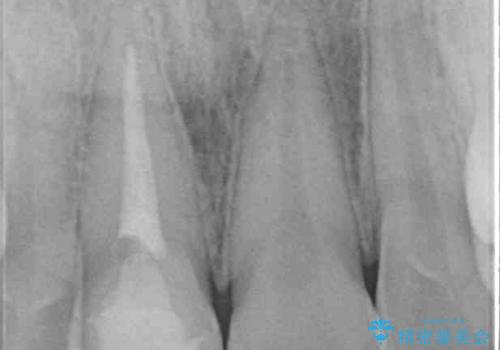

土台に含まれている金属も含め、口腔内の金属は全て除去し、根管治療が必要な歯は根管治療を行い、オールセラミッククラウンやセラミックインレーにて治療することとしました。

途中来院されない時期があったため、初診から終了まで期間がかかりましたが、根管治療を行った歯の根尖病変はいずれも改善を確認することができました。